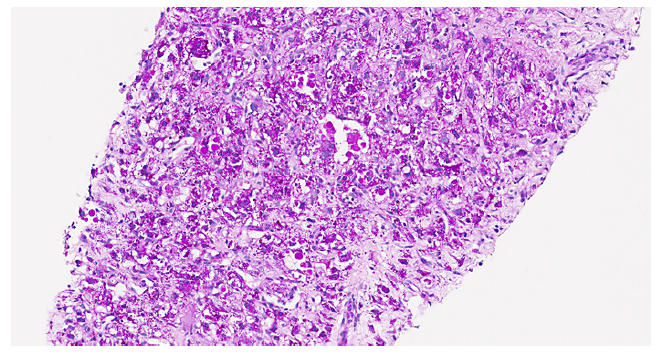

The collected material consisted of two biopsy cylinders in total with 18 mm width, showing hepatic tissue with normal architecture and signs of compression in relation to the presence of an adjacent space-occupying lesion. The lesion was well demarked from the liver tissue by a fine connective tissue band and was composed by a highly variable cell population (shown in Fig. 1), exhibiting multinucleated giant cells with enlarged irregular hyperchromatic nuclei, eosinophilic clear cytoplasm with fading limits. There were PAS-positive hyaline globules (shown in Fig. 2, 3), and other smaller cells with epithelioid, stellated, or spindled configuration, supported by a myxoid richly vascularized stroma. No mitotic activity was detected.

Fig. 1 Lesion with severely pleomorphic cell population (haematoxylineosin, original magnification, ×200).